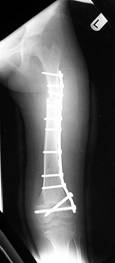

Follow Up

Converted to immediate exchane nail after 65mm lengthening

Consolidation regenerated

Leg length equalised but with different knee height